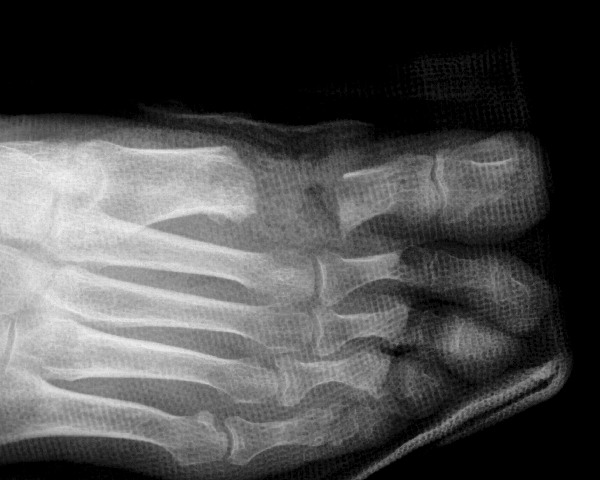

There are many instances when it is appropriate for the foot and ankle surgeon to use bone grafts in order to enhance a patient’s clinical outcome. When it comes to reconstructive osteotomies for angular realignment, arthrodeses and the repair of nonunions and cystic bone lesions, these are often best performed with procedures that take advantage of the many desirable features of bone grafts and, more recently, bone graft substitutes. Before discussing the details of bone graft substitutes, it is helpful to review the bone graft options that are available to the surgeon. These options include: cancellous and/or cortical bone, allogeneic (typically freeze-dried) cadaver bone and autogenous bone. Cancellous bone offers a porous, osteoconductive environment and ease of incorporation. However, it conveys limited structural strength and ability to retain fixation devices. Cortical bone, on the other hand, offers tremendous structural integrity, but it is slow to incorporate in comparison to cancellous bone. Allogenic bone implants offer ease of use, ready availability and provide a wide range of configurations that include cortical and cancellous bone in various proportions. However, despite rigorous measures related to the procurement and preparation of allogeneic tissue products, there remains a very small but real risk of disease transmission and hypersensitivity reaction.1,2 The autogenous corticocancellous bone graft, which is typically harvested from the iliac crest, remains the gold standard for comparison of all other grafting materials. In reconstructive foot and ankle surgery, the calcaneus offers a reliable source of autogenous bone graft material. Unfortunately, however, autogenous sources of corticocancellous bone are limited and there is distinct morbidity associated with harvesting autogenous bone. Banwart et al., performed a meta-analysis of the related literature and observed that use of autogenous iliac crest bone grafts was associated with a 25 to 45 percent complication rate. They also noted that 40 percent of patients related harvest site pain up to five years postoperatively.3 For these reasons, the emergence of bone graft substitutes for enhancement or augmentation of bone grafting procedures, as well as the techniques of bone callus distraction, have proven to be of great service in recent years.